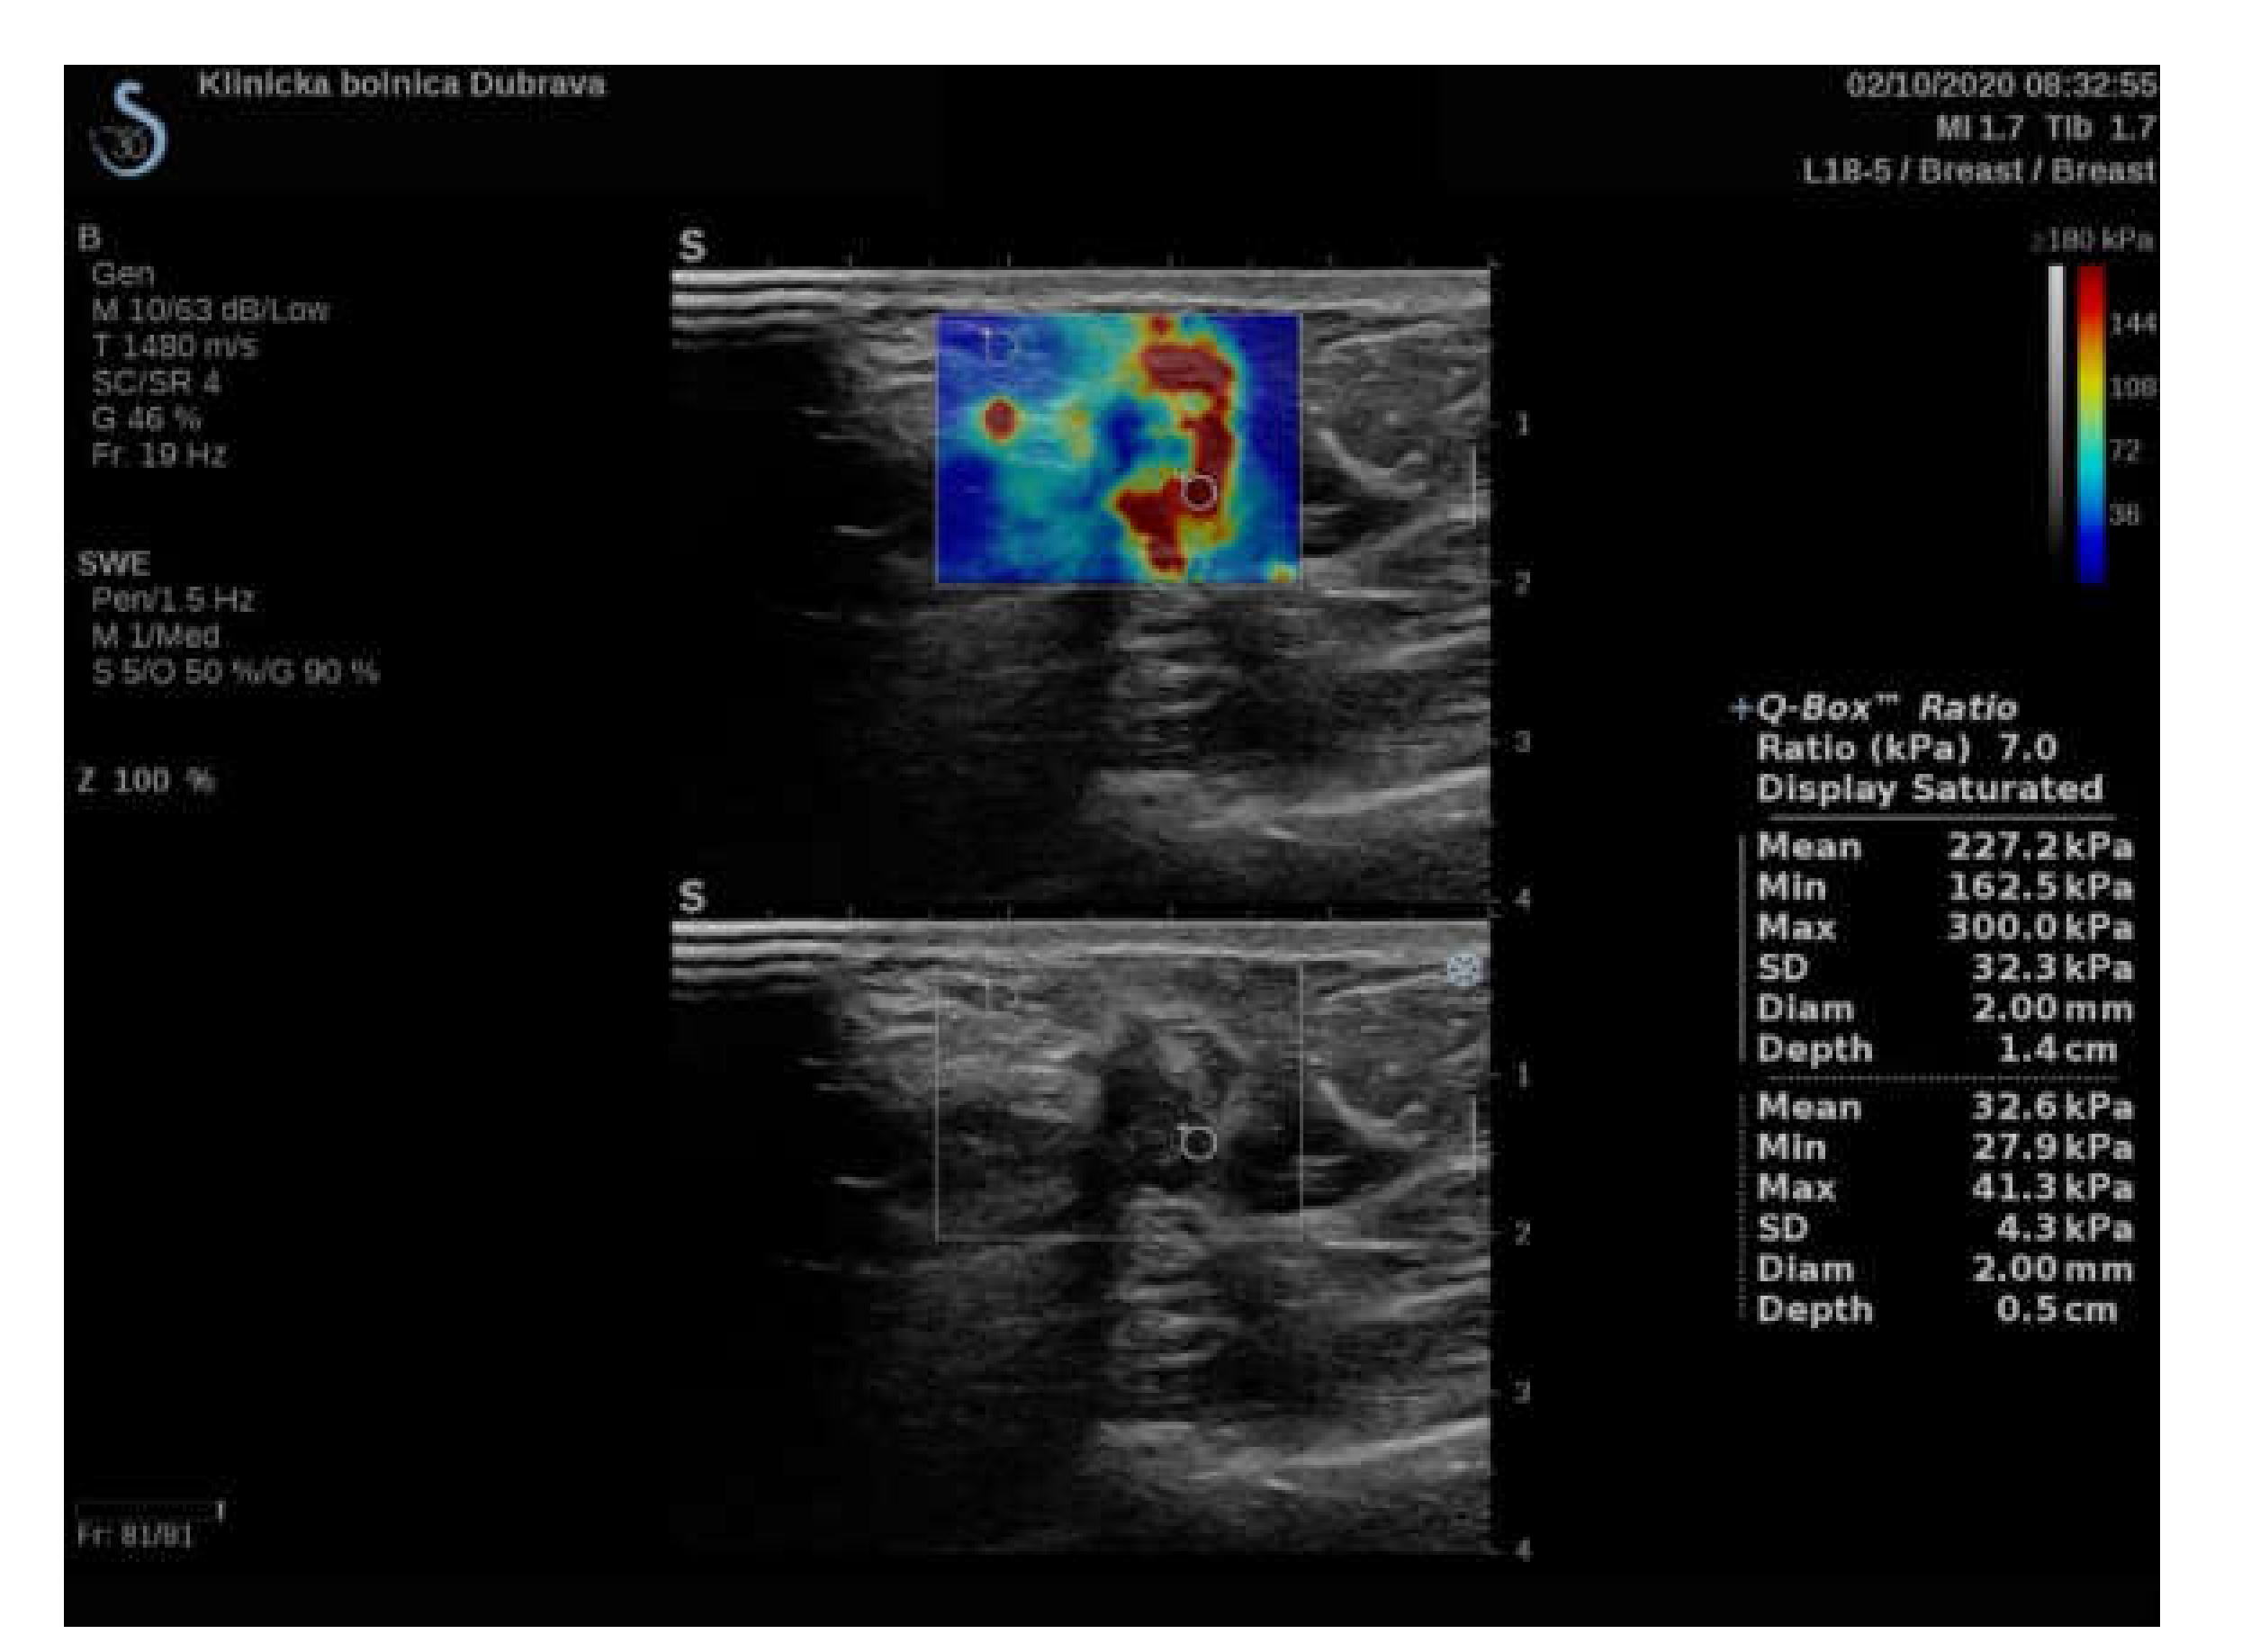

| Variable | Lesion Size < 15 mm | Lesion Size ≥ 15 mm | p Value | Correlation with Lesion Size as a Cont. Variable |

|---|---|---|---|---|

| Nm of patients | 95 | 55 | - | - |

| Emean ROI 2 mm (kPa) | 141.8 IQR (119.6–165.9) | 161.7 IQR (134.95–190.6) | 0.003 * | Rho = 0.4; p < 0.001 * |

| Sd ROI 2 mm (kPa) | 16.6 IQR (11–23) | 16.6 IQR (11.35–23.3) | 0.729 | Rho = 0.18; p = 0.030 * |

| Coeff. var. ROI 2 mm (%) | 11.1 IQR (8.08–16.42) | 10.1 IQR (6.7–16.32) | 0.245 | Rho = −0.01; p = 0.894 |

| Emin ROI 2 mm (kPa) | 104.9 IQR (79.4–127.4) | 123.8 IQR (91.3–154.6) | 0.015 * | Rho = 0.3; p < 0.001 * |

| Emax ROI 2 mm (kPa) | 171.8 IQR (137.9–192) | 192 IQR (171.85–221.6) | 0.001 * | Rho = 0.44; p < 0.001 * |

| e-ratio ROI 2 mm | 8.8 IQR (6.6–12.75) | 8.6 IQR (7.5–12.95) | 0.201 | Rho = 0.19; p = 0.023 * |

| Emean ROI 4 mm (kPa) | 111.3 IQR (89.15–135.55) | 128.6 IQR (111.9–161.8) | 0.001 * | Rho = 0.42; p < 0.001 * |

| Sd ROI 4 mm (kPa) | 31 IQR (21.9–37.65) | 32.8 IQR (24.15–40.1) | 0.256 | Rho = 0.21; p = 0.009 * |

| Coeff. var. ROI 4 mm (%) | 25.7 IQR (20.72–34.14) | 22.7 IQR (17.93–32.1) | 0.154 | Rho = −0.1; p = 0.219 |

| Emin ROI 4 mm (kPa) | 49.3 IQR (32.3–66.9) | 57.2 IQR (40.05–82) | 0.063 | Rho = 0.26; p = 0.002 * |

| Emax ROI 4 mm (kPa) | 171.8 IQR (137.9–192) | 192 IQR (171.85–214.6) | 0.001 * | Rho = 0.43; p < 0.001 * |

| e-ratio ROI 4 mm | 6.3 IQR (4.55–8.8) | 6.3 IQR (4.95–10.05) | 0.638 | Rho = 0.14; p = 0.092 |

| Emean ROI 6 mm (kPa) | 89.4 IQR (69.8–110.1) | 105.1 IQR (89.65–129.8) | 0.001 * | Rho = 0.4; p < 0.001 * |

| Sd ROI6 mm (kPa) | 34.5 IQR (24.75–43.45) | 39.7 IQR (32.95–46.55) | 0.005 * | Rho = 0.39; p < 0.001 * |

| Coeff. var. ROI6 (kPa) | 38.4 IQR (28.82–46.59) | 35.7 IQR (29.24–44.9) | 0.785 | Rho = 0.01; p = 0.942 |

| Emin ROI 6 mm (kPa) | 23.1 IQR (15.1–38.45) | 25.4 IQR (10.85–41.1) | 0.685 | Rho = 0.09; p = 0.295 |

| Emax ROI 6 mm (kPa) | 171.8 IQR (137.9–192) | 192 IQR (171.85–221.6) | 0.001 * | Rho = 0.43; p < 0.001 * |

| e-ratio ROI 6 mm | 4 IQR (3.15–5.7) | 3.4 IQR (2.85–5.35) | 0.335 | Rho = −0.05; p = 0.527 |